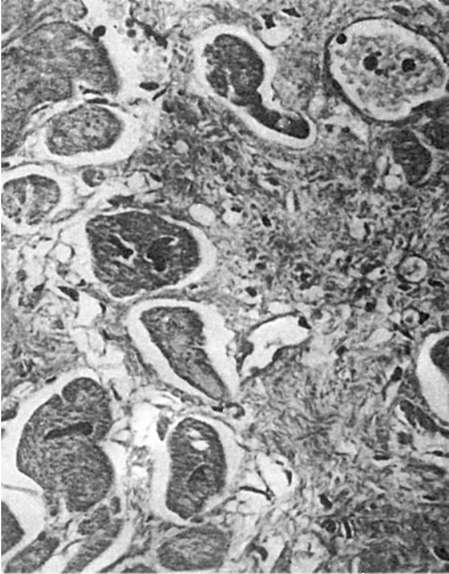

Регенерация в организме: удивительные способности человека